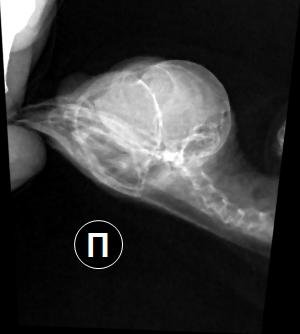

Ирина_2020 Опубликовано 6 февраля, 2023 Автор #71 Опубликовано 6 февраля, 2023 В декабре стрижик снова заболел - плохое самочувствие и над глазом вскочила твердая шишка. Решили, не дожидаясь приема и результатов посева снова давать Панцеф (Супракс), к которому по прошлому посеву была чувствительность, бактериофаг клибсиелл и ирунин. Новый посев показал правильность этого решения, месяц пропили курс и стриж, кажется, выздоровел. За шишкой стали наблюдать - ее размер не менялся. Дней восемь назад ему снова стало становиться хуже, взяли мазок из горла на посев и снова стали давать Панцеф. 2 февраля на приеме у врача отдали мазок, сделали рентген, на котором видно, что глазные и носовые каналы эта гнойная пробка не задевает, но больше покажет только КТ. Иссечь и вычистить, по словам врача - опасно, слишком близко к мозгу и много мелких сосудов. Сейчас 5 дней пьем панцеф, бактериофаг, ирунин, гепатовет (для защиты печени), линекс и мелоксидил. Глаза тоже воспалены и с трудом открываются - их промываем гиланом и тобрексом. Позавчера вид стрижа был очень больной, вчера немного улучшилось состояние, а сегодня целый день он вялый, каким никогда раньше не был. Обычно спит в одном уголке спальной коробки, а сегодня постоянно перемещается по ней, как будто ищет удобное место... Может, а/б не работает и заменить его на имипенем или амикацин, к которым в прошлом посеве тоже была чувствительность?